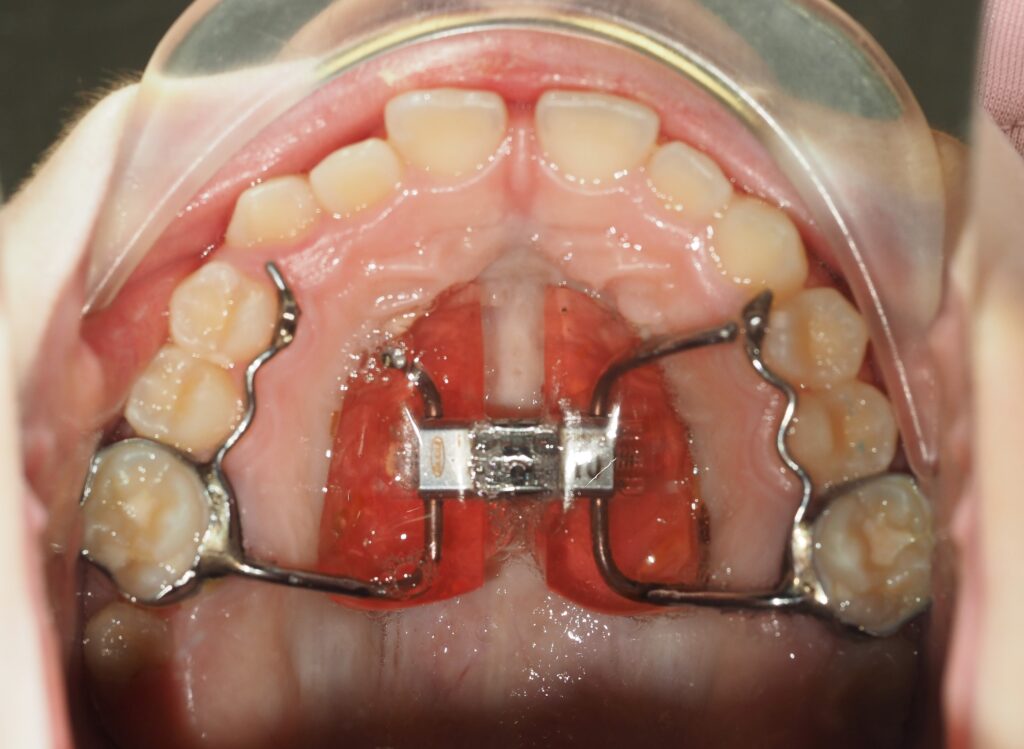

Hay que pensar que el suelo de las fosas nasales, es el techo de la cavidad oral ( el paladar). Un niño que no usa la nariz, ES UN RESPIRADOR ORAL respira por la boca) y presentará con el tiempo una nariz pequeña, poco desarrollada, narinas frontales y un paladar estrecho.

¿y porqué un paladar estrecho?

El desarrollo del maxilar superior depende :

- de la respiración nasal: el paso del flujo de aire nasal

- y de una buena posición de reposo de la lengua, cuyo dorso ha de estar apoyado en el paladar. Cuando un niño respira por la boca y no usa la nariz, para poder llevar esa respiración oral la lengua está en posición baja, no apoya su dorso contra el paladar ( en la respiración nasal sí) y por eso se ve afectado su desarrollo transversal.

- el paladar se queda estrecho por el NO uso de la nariz, y porque la lengua, cuyo dorso tendría que apoyarse en el paladar ( otro de los factores que inducen a un buen desarrollo del maxilar superior) se queda en una posición baja para permitir esa respiración oral, por lo tanto el maxilar no se desarrolla bien, se queda estrecho y por mucho que le digamos dónde ha de colocar la lengua, no lo hará porque ya no cabe en ese paladar .